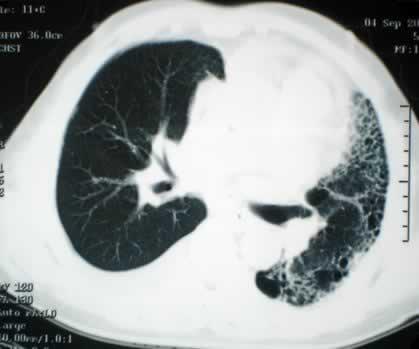

接受心肺植入手术的是十三岁的女孩阿尔穆德纳-加尔韦斯,她因双肺纤维性病变,呼吸十分困难。这家医院心血管外科专家二十七日午夜开始对女孩施行移植手术,手术复杂艰难,持续到二十八日凌晨四点。据手术医生说,手术后女孩感觉良好。